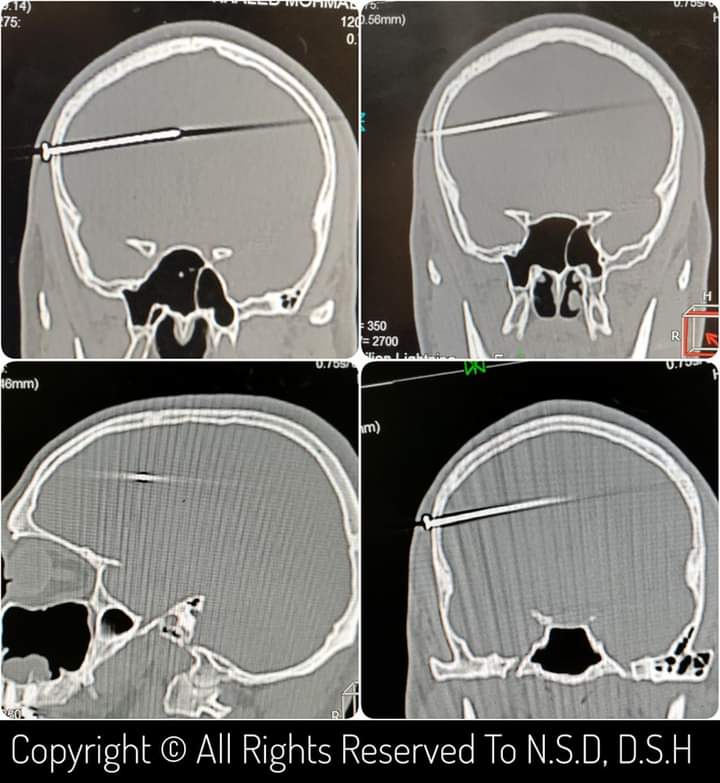

وبعد عمل أشعة مقطعية على المخ تبين وجود جسم غريب (مسمار) مخترق لعظام الجمجمة ونصف حجم المخ في إصابة مباشرة لشريان من شرايين المخ.

وبسؤال المريض والمرافقين أكدوا أنه أثناء العمل حدث انزلاق لا إرادي لدباسة هوائية خاصة بالمسامير وعلى أثرها تطاير مسمار منها مخترقا لعظام جمجمة ومخ الشاب، وتم على الفور تحضير المريض لجراحة دقيقة لاستخراج الجسم المعدني.